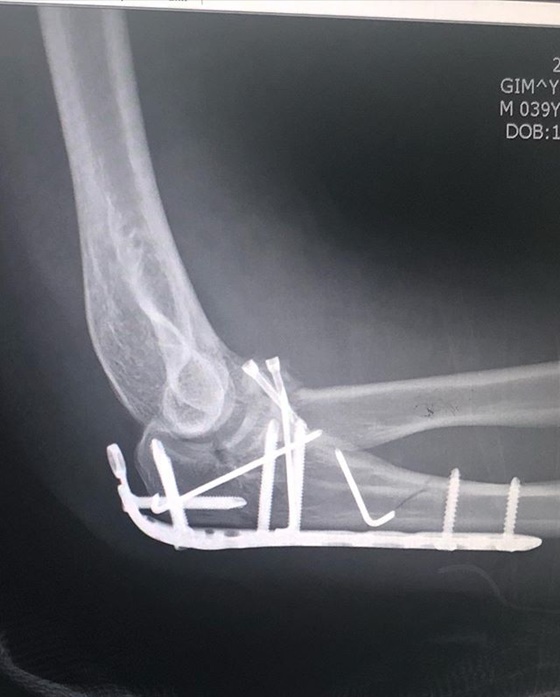

이와 함께 철심을 박은 엑스레이 촬영 결과도 직접 공개해 눈길을 끈다.

개코는 "뜻하지 않게 로봇팔이 되어 버렸네요. 좋으신 의료진분들 덕에 수술은 잘 되었습니다"라며 수술 후기를 전했다.

소속사 아메바컬쳐에 따르면 개코는 오른팔 골절상을 당해 수술을 받게 됐다.